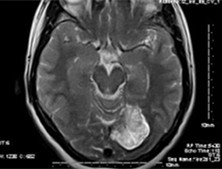

小脑幕脑膜瘤

小脑幕脑膜瘤是指附着在小脑幕上(包括幕切痕和窦汇区)的肿瘤基底的脑膜瘤,可以发展...